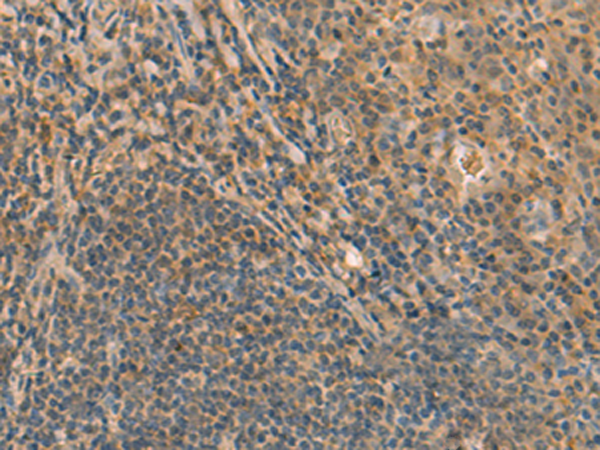

分类: 科研抗体货号: P09976别名: TIC; EFA6B应用: IHC反应种属: Human, Mouse